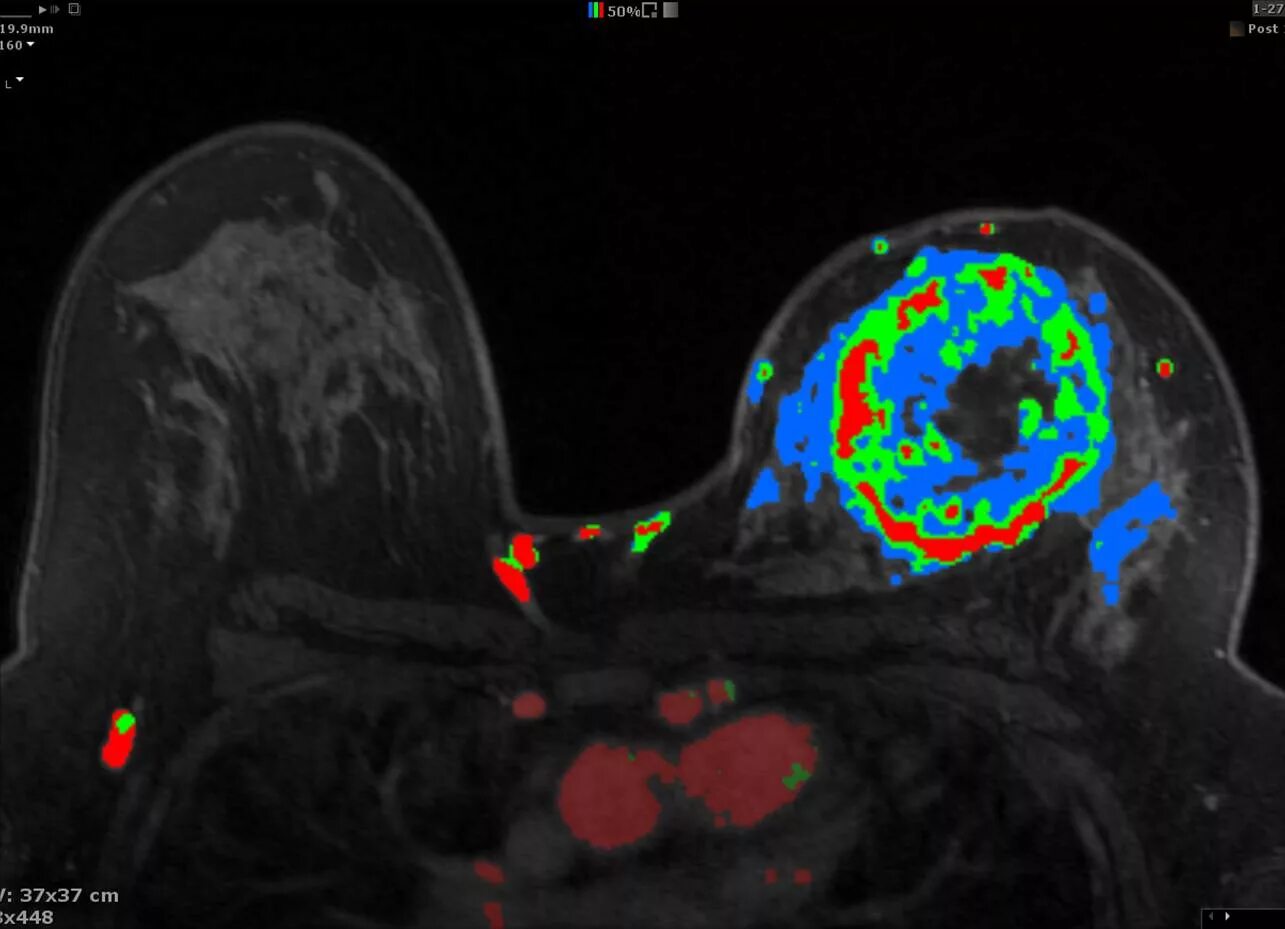

Мрт молочных желез